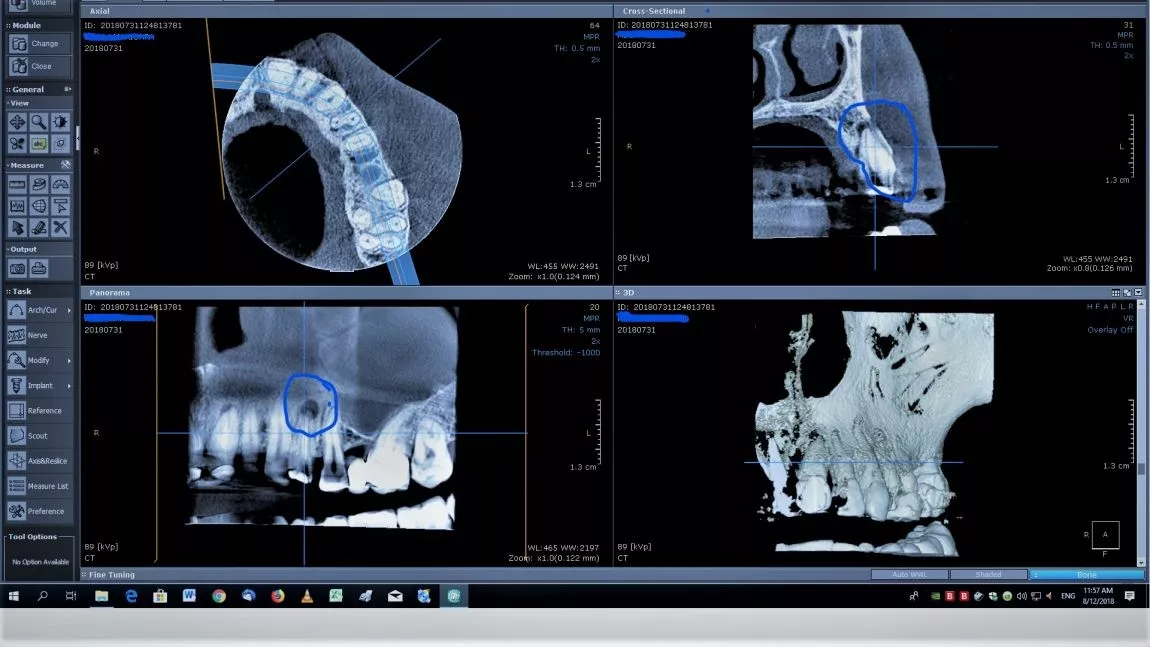

Comparație radiografie 2D – 3D

În ceea ce privește implantul, siguranța înserării este asigurată de măsurătorile efectuate în modul tridimensional și de simulările efectuate anterior înserării.

Un alt exemplu este identificarea mărimii unui granulom. În funcție de mărimea acestuia, tratarea afecțiunii se rezolvă edodontic sau chirurgical.